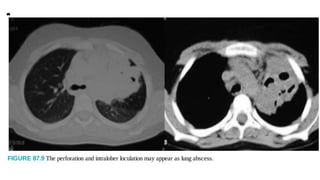

• Massive Hemoptysis

Patients may present with severe hemoptysis. An emergency

chest CT may demonstrate a parenchymal

mass, often without any sign of hydatid disease (Fig. 87.17). An

emergency bronchoscopy should be

performed in the operating room readied to continue emergency

surgery (Fig. 87.18). As a rule, these